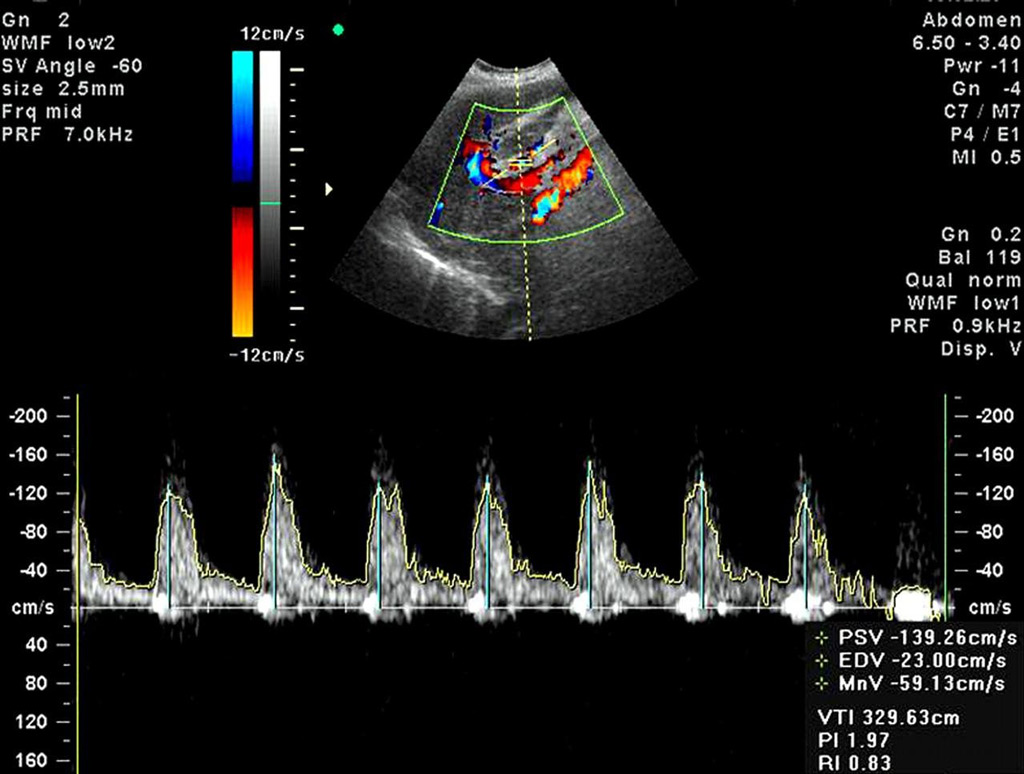

Хотя эхокардиография является высокоинформативным методом исследования, она не всегда может предоставить все необходимые данные для диагностики. В таких ситуациях дополнительно проводится допплерометрия. Этот анализ помогает определить, как кровь циркулирует в сердце. Неправильные пропорции могут указывать на проблемы с работой клапанов. Основная задача данного исследования — оценить способность сердца к сокращению или нормокинезису. Нормальные показатели для здоровой сердечной мышцы:

- трансмитральный приток крови — до 1,3 м/с;

- транспульмональный — от 0,6 до 0,9 м/с;

- транскуспидальный — максимум 0,7 м/с;

- кровоток в конечных отделах сердца — от 0,7 до 1,1 м/с.